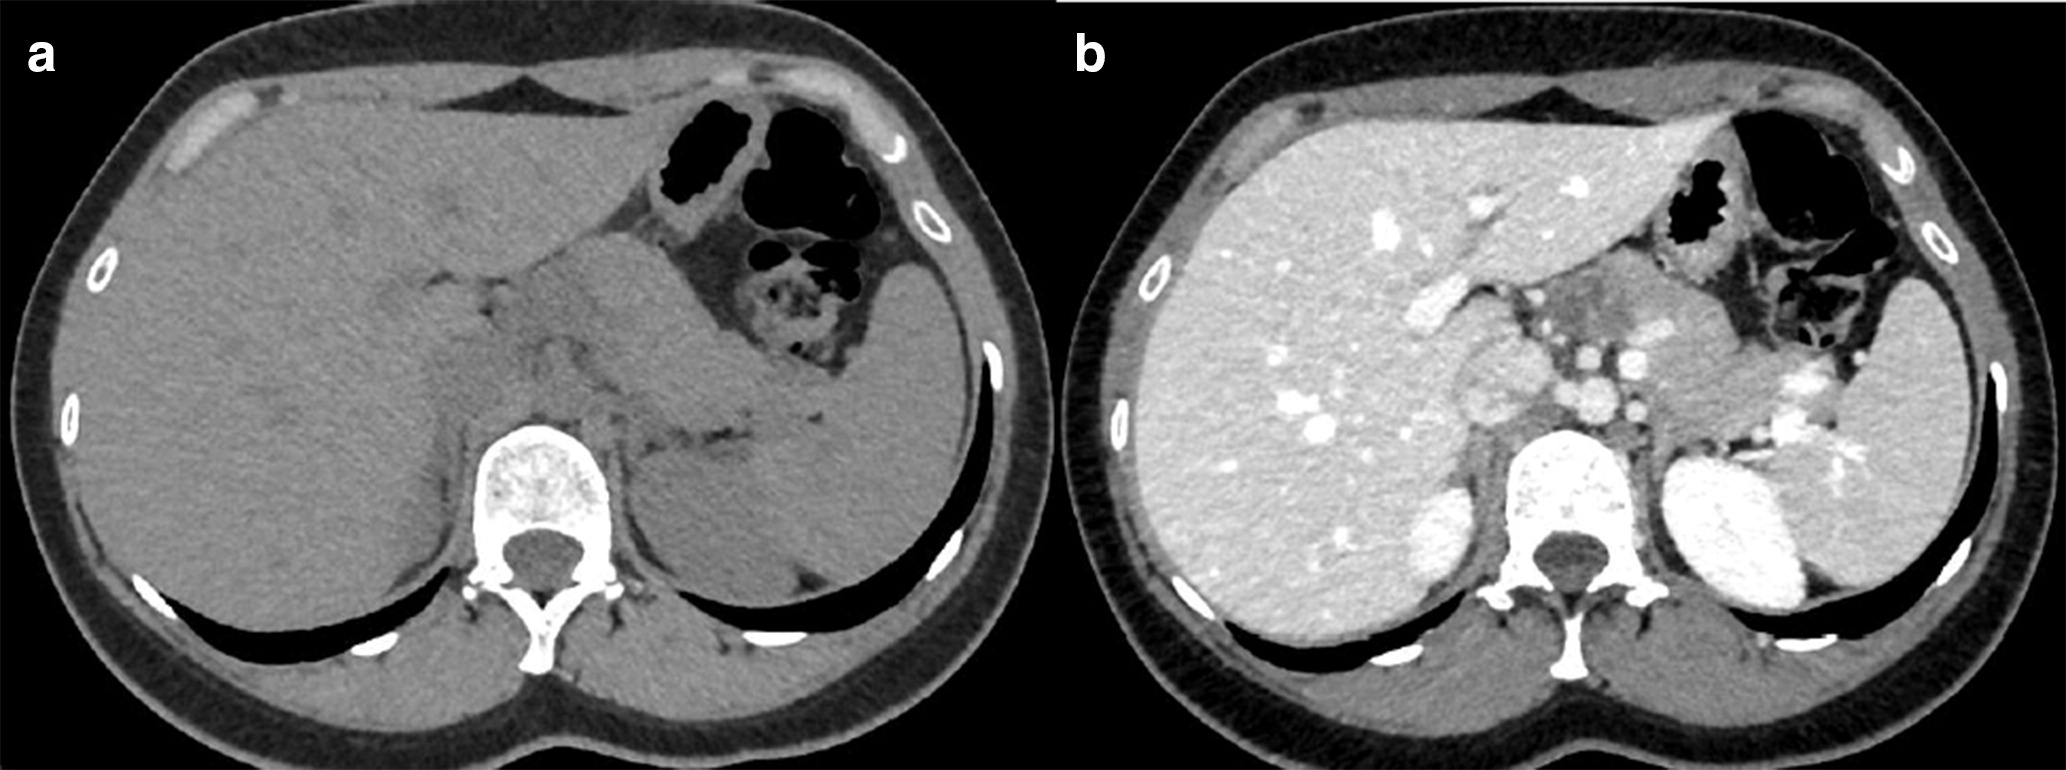

A 70-year-old man with a known diagnosis of an infrarenal abdominal aortic aneurysm (AAA) underwent repair with a bifurcated aorto-bi-iliac endovas…